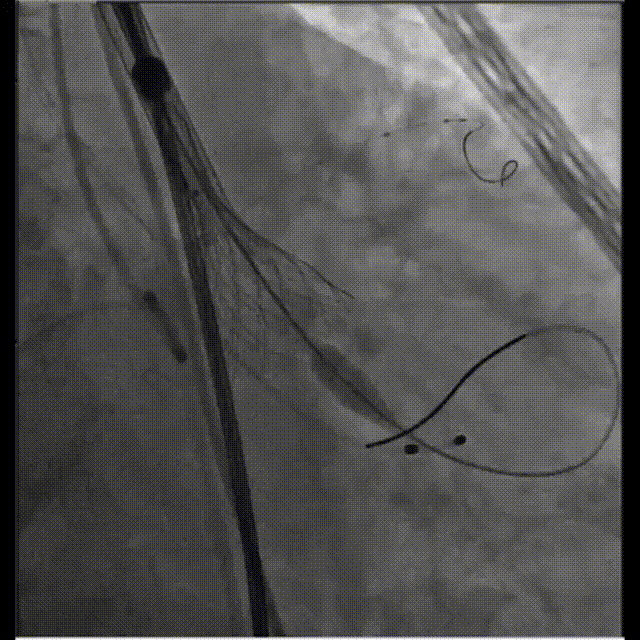

球囊预扩

球囊预扩评估冠脉有阻塞风险,预埋导丝保护

位置偏深回收调整,进行第二次释放